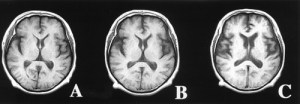

I’ll end this post with a progressive-over-time brain scan image of Lewy Body dementia (the source is http://www.neurology.org/). A picture sometimes is worth one thousand words, especially when I consider the fact that my mom had vascular dementia, Lewy Body dementia, and Alzheimer’s Disease and this picture shows the damage to the brain from just one of those three diseases. What an uphill battle her last few years were and she fought it bravely and well right up to the end.